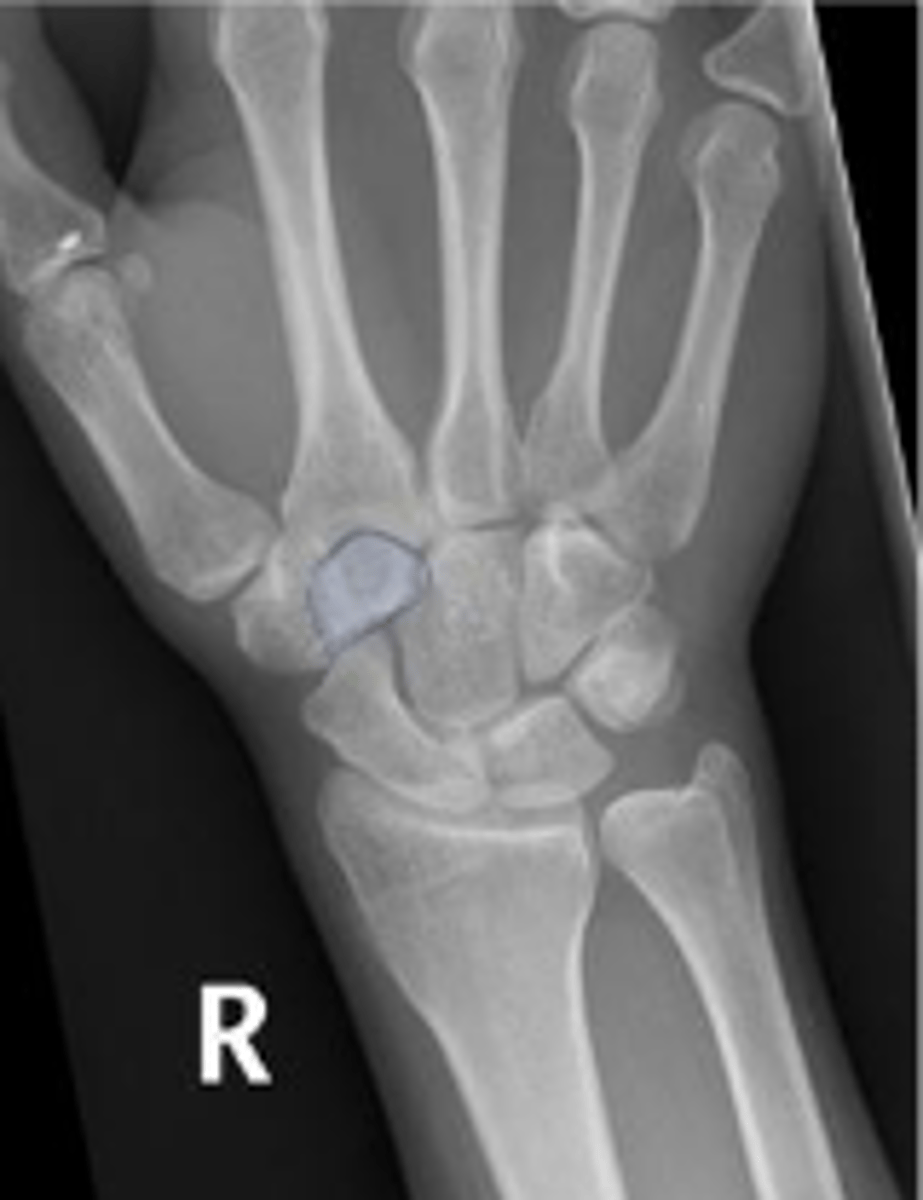

PA of the left wrist

What is the name of the radiographic view?

Left scaphoid

What is outlined?